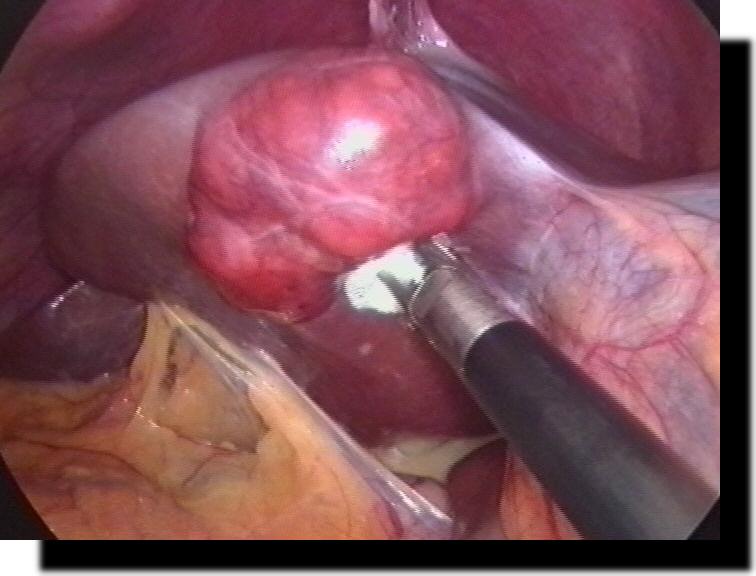

Leberadenom

Leberhämangiom

Lebermetastase

Ovarialkarzinom

Peritoneal-Karzinose

Cul-de-sac